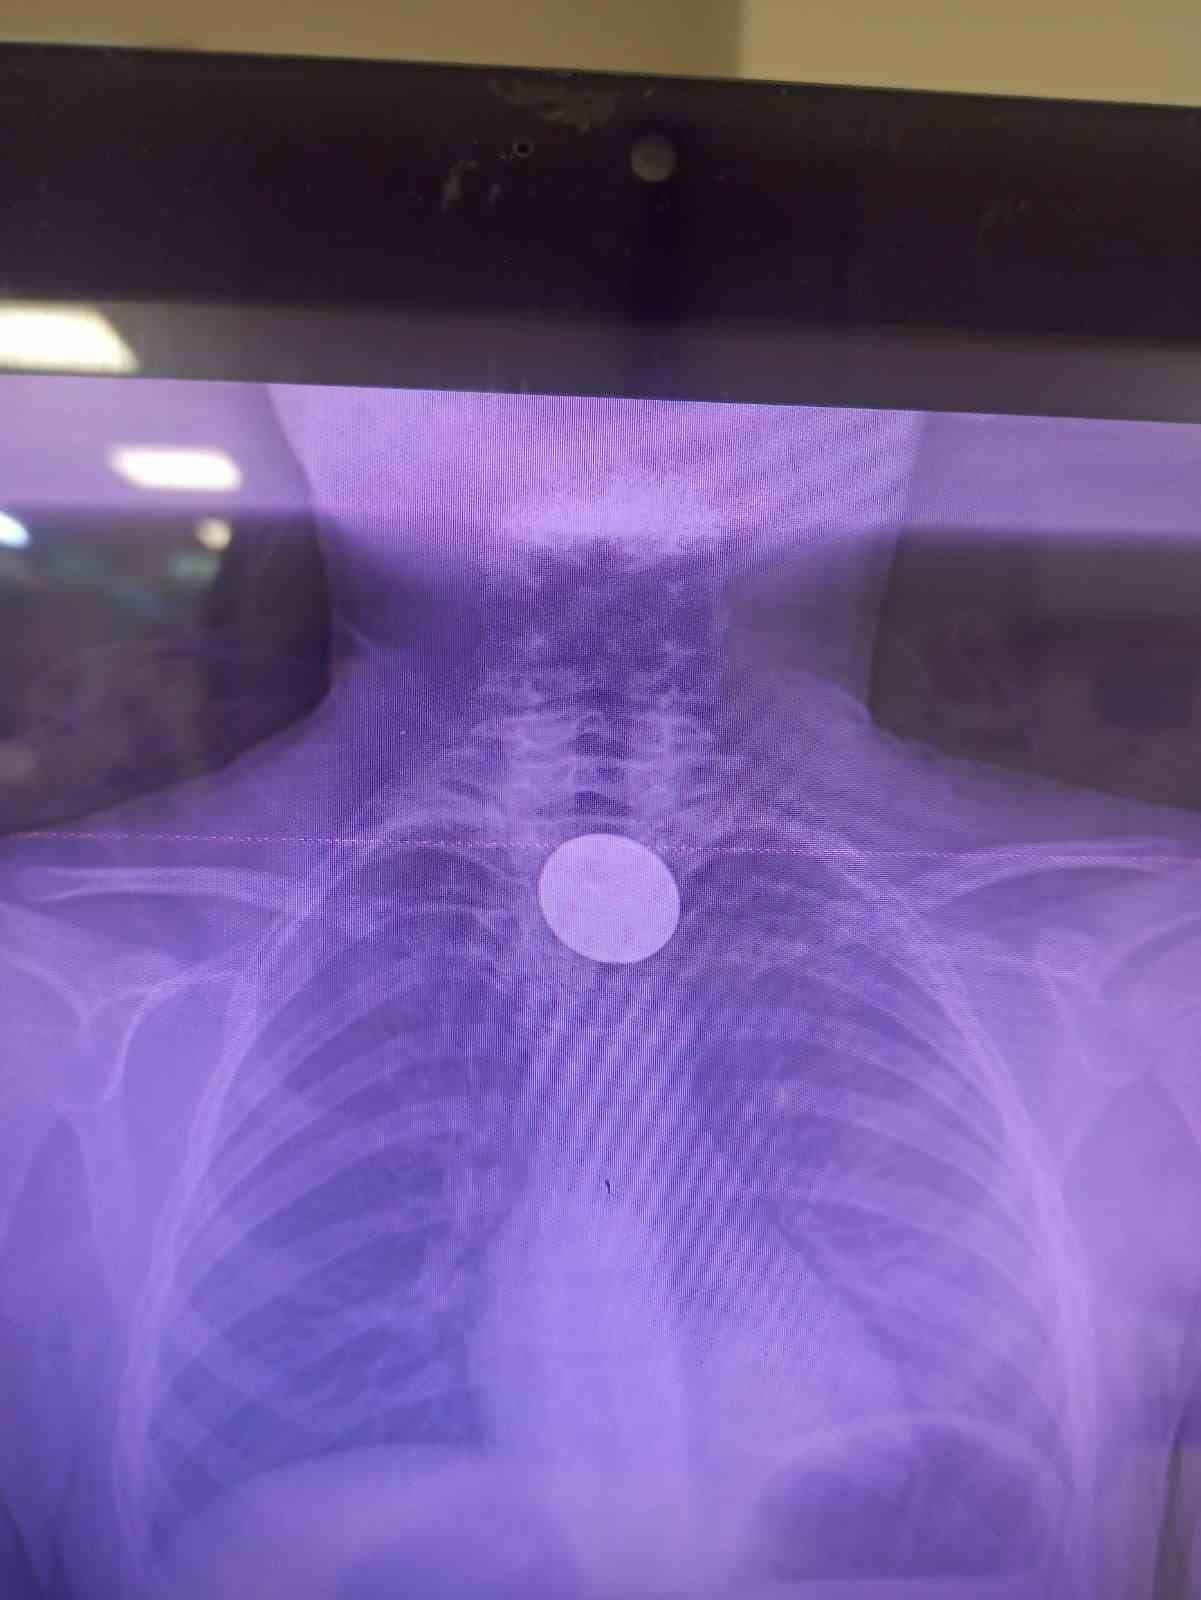

Siirt'te 8 yaşındaki Y.K., boğazına değeri 5 lira olan bir madeni para kaçması sonucu hastaneye başvurdu. Siirt Eğitim ve Araştırma Hastanesi'nde yaşanan bu olay, doktorların hızlı müdahalesi sayesinde başarılı bir şekilde sonuçlandı.

Yabancı Cisim Yutma Gerçeği

Ailesi tarafından hastaneye getirilen çocuk, yabancı cisim yutma şikayeti ile acil servise alındı. Yapılan detaylı incelemeler sonucunda, madeni paranın yemek borusuna kadar ilerlediği belirlendi. Uzman ekip, gastroenteroloji doktoru Dr. Yaren Dirik ve kulak burun boğaz hekimi Yasin Gökçınar tarafından gerçekleştirilen operasyonla para çıkarıldı.

Siirt Eğitim ve Araştırma Hastanesi Başhekim Yardımcısı Uzman Dr. Burak Özkan, çocuklarda yabancı cisim yutma vakalarının ciddi riskler taşıdığını vurgulayarak, "Hastanemize başvuran 8 yaşındaki hastamızın yemek borusuna kaçan madeni para, ekiplerimizin koordineli çalışması ile sorunsuz bir şekilde çıkarılmıştır. Tedavi süreci iyi geçti ve hastamız taburcu edilmiştir" şeklinde konuştu.